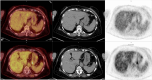

Gastric Metastases From Invasive Breast Lobular Carcinoma, Identified by [18F]FDG PET/CT, 20 Years After Primary Diagnosis: A Case Report

Invasive lobular carcinoma (ILC) of the breast is a rare subtype of breast cancer with distinct metastatic patterns. Although gastrointestinal metastases are rare, they can occur years after initial treatment. This case highlights the diagnostic challenges and management of late-onset gastric metastases. A 68-year-old woman with a history of ILC treated 20 years earlier presented with elevated tumor markers. [18F]fluorodeoxyglucose positron emission tomography/computed tomography (FDG PET/CT) revealed hypermetabolic lesions in the stomach and esophagus in this patient with previously diagnosed gastritis and gastroesophageal reflux disease. Endoscopy and biopsies confirmed the presence of metastatic ILC in the stomach. Adjustment of treatment, including exemestane and everolimus, followed by paclitaxel and tamoxifen, resulted in partial disease control. Late-onset gastrointestinal metastases of ILC are uncommon and require special vigilance, particularly in patients with associated benign gastrointestinal pathologies, which may delay diagnosis. Persistent or new-onset gastrointestinal symptoms in breast cancer patients warrant thorough evaluation, including FDG PET/CT imaging and histological confirmation.